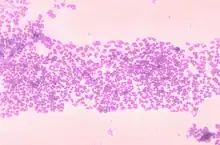

Micrococcus (mi’ krō kŏk’ Əs) is a genus of bacteria in the Micrococcaceae family. Micrococcus occurs in a wide range of environments, including water, dust, and soil. Micrococci have Gram-positive spherical cells ranging from about 0.5 to 3 micrometers in diameter and typically appear in tetrads. They are catalase positive, oxidase positive, indole negative and citrate negative. Micrococcus has a substantial cell wall, which may comprise as much as 50% of the cell mass. The genome of Micrococcus is rich in guanine and cytosine (GC), typically exhibiting 65 to 75% GC-content. Micrococci often carry plasmids (ranging from 1 to 100 MDa in size) that provide the organism with useful traits.